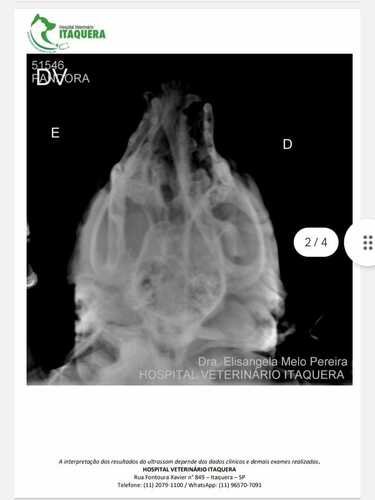

Oi, eu sou a Deise, dona da Pandora (cachorra acidentada) e estou aqui pedindo ajuda para arrecadar R$3.000,00 para realizar uma cirurgia de emergência na mandíbula devido a um acidente provocado por um atropelamento no dia 31 de março de 2024 (domingo de Páscoa). A cirurgia é de extrema emergência, pois a Pandora não consegue comer nem beber água, pois está com a boca extremamente quebrada. Já levei em vários veterinários públicos, mas os mesmos não realizam esse tipo de cirurgia, somente no particular, e o mais em conta que consegui foi R$3.000,00. Não tenho condições de arcar com esse valor, por isso peço a ajuda de todos.